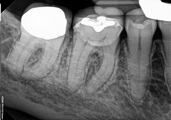

Treatment Examples

Conventional endodontic treatment with alloy core build up

All Treatment performed by Dr. Brian A. Christopherson